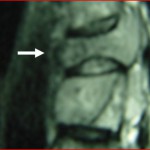

Η Ρομποτική Χειρουργική ενισχυόμενη από την Τεχνητή Νοημοσύνη αποτελεί μεγάλη εξέλιξη στη θεραπευτική αγωγή. Ο συνδυασμός αυτών συμβάλει ουσιαστικά: α. Στον προεγχειρητικό σχεδιασμό β. Στην επιτέλεση της χειρουργικής πράξης με την μέγιστη δυνατή ακρίβεια γ. Στη μείωση των επιπλοκών δ. Στην μείωση του χειρουργικού χρόνου ε. Στον ουσιαστικό περιορισμό της προσλαμβανόμενης ακτινοβολίας από το προσωπικό